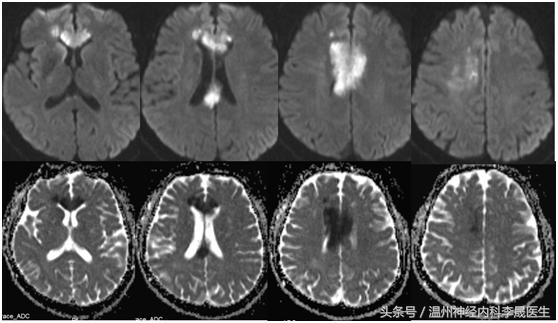

先看个病例,女,46岁,主诉;反应迟钝、走路不稳半月。既往史;“高血压”病病史3年,不规律服药,血压控制不详

查体:神经系统:左上肢及右侧肢体肌力5级,左下肢肌力4级,左上肢指鼻试验欠准,与右上肢完成同一动作时笨拙,有时不自主阻挡右手动作,双侧肢体感觉正常,行走似稍宽基底。病理反射未引出。NIHSS评分3分

附上一组经典的CT片跟MRI片